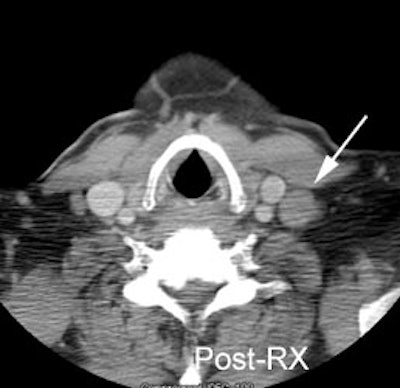

Residual mass post-therapy: The patient shown below had received chemotherapy for lymphoma. There was a residual left neck mass following completion of therapy. A FDG PET exam revealed persistent metabolic activity within the mass concerning for residual tumor. Based upon the FDG exam findings, the patient's management was changed to include additional chemotherapy. |

|